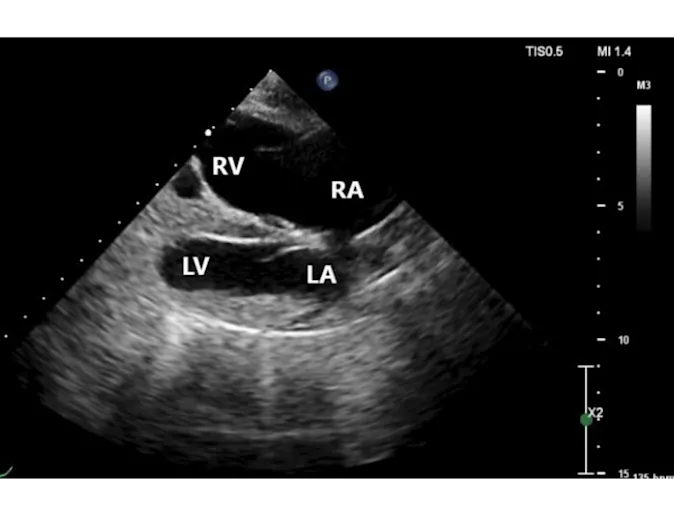

Patent Ductus Arteriosus

Diagnostic Imaging

The patient presented to the GCVS Cardiology Service for evaluation of a heart murmur heard at a veterinary visit as a young puppy. No clinical signs at home.